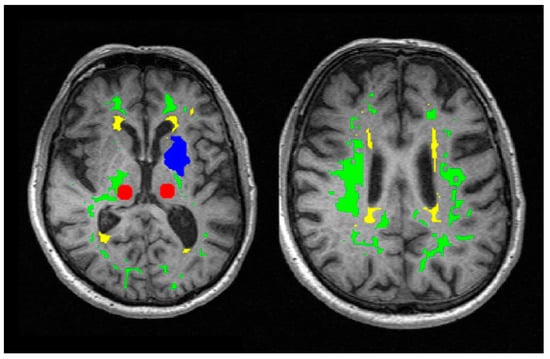

4.3.3. Structural Image Processing

4.3.4. Quantitative Image Processing